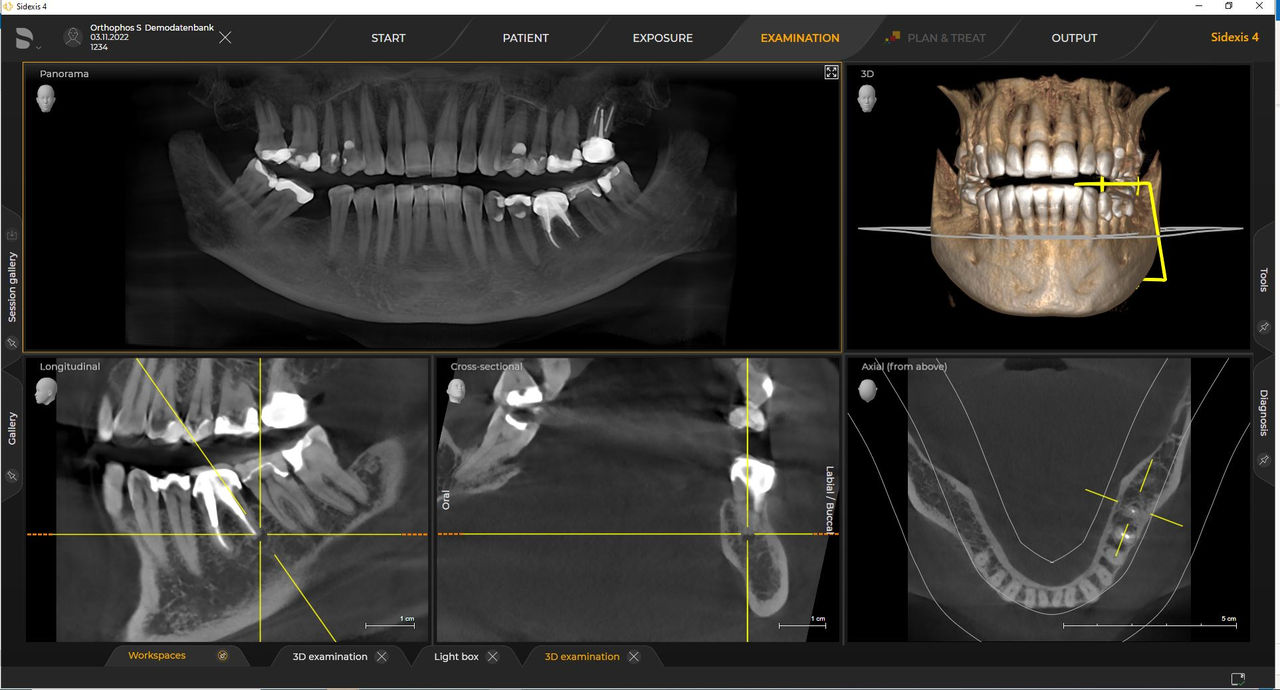

Dentsply Sirona Röntgengeräte arbeiten exklusiv mit Sidexis 4. Aber die Datenmigration von Sidexis XG zu Sidexis 4 ist sehr einfach. Wir empfehlen den Wechsel zu Sidexis 4, um die vollen Vorteile des digitalen Prozesses mit den neuesten Werkzeugen zu erleben.